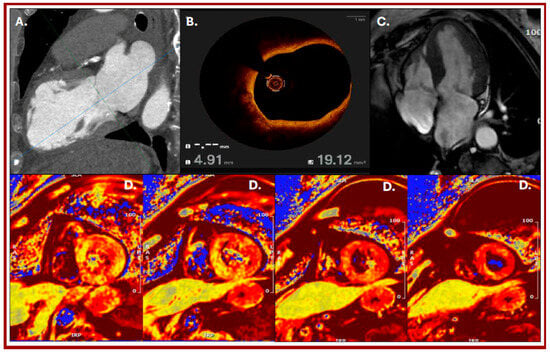

Multimodality Imaging in the Diagnosis of an Early Tako-Tsubo Syndrome Recurrence

by Maria Letizia Berloni, Andrea Daniele Annoni, Marco Moltrasio, Andrea Baggiano and Gianluca Pontone

We report the case of an 80 yo female patient with cardiovascular risk factors and previous diagnosis of Tako-Tsubo syndrome, who was referred to our institution one year after a previous diagnosis, due to symptoms suggestive of acute coronary syndrome (SCA) after severe [...] Read more.

We report the case of an 80 yo female patient with cardiovascular risk factors and previous diagnosis of Tako-Tsubo syndrome, who was referred to our institution one year after a previous diagnosis, due to symptoms suggestive of acute coronary syndrome (SCA) after severe emotional stress. After ruling out suspected CAD by cardiac computed tomography (CCT) and subsequent invasive coronary angiography (ICA) confirming no significant stenosis but presence of vulnerable plaque, the patient underwent further investigation by cardiac magnetic resonance (CMR) that confirmed a clinical picture compatible with recurrence of Tako-Tsubo syndrome. Our case underlines the importance of multimodality imaging to guide diagnosis and treatment in this specific clinical scenario. Full article